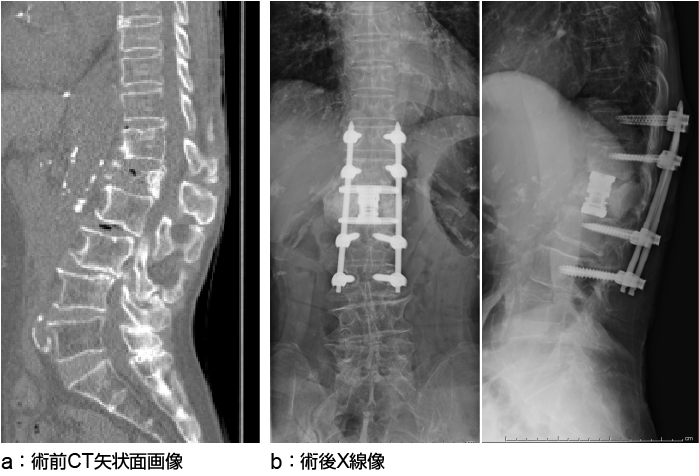

椎体形成術

骨癒合不全部に骨セメントを注入する椎体形成術

a:X線正面像

b:X線側面像

後方固定術を併用した椎体形成術

椎体形成術に椎体インストゥルメンテーションを併用した手術。